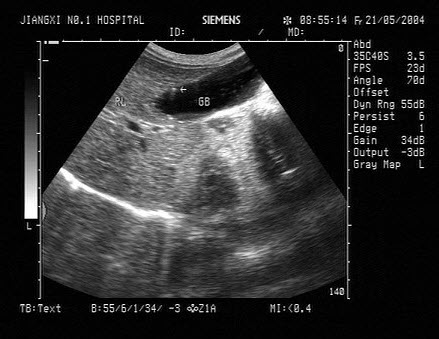

17、单项选择题

男,64岁,右上腹反复疼痛不适数10年,加重5天。声像图如图所示,诊断为()